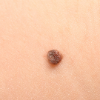

Первичный прием врача дерматовенеролога

2300 руб.